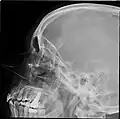

![]() Lateral projection of the paranasal sinuses | |

Paranasal sinuses radiograph (lateral) -